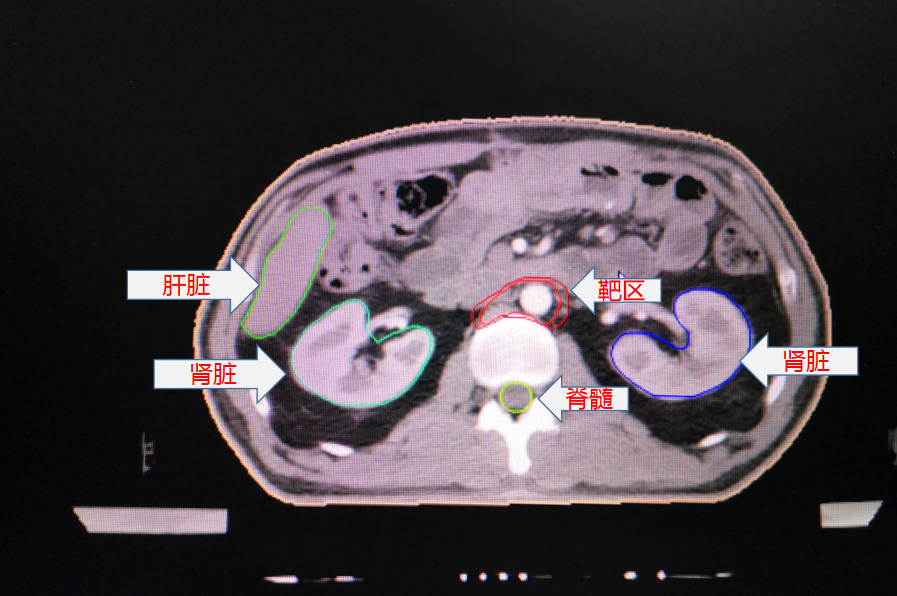

胃癌術後靶區勾畫示例:

其中,胃癌術後規範性預防性放(fàng)療為(wèi)我院首次開展。放(fàng)療前,嚴格按腫瘤放(fàng)療規範和靶區定義勾畫靶區範圍,放(fàng)療期間(jiān),在靶區照射野獲得足夠目标劑量同時(shí),危及器(qì)官受量均在劑量限制标準範圍之内,病人(rén)周圍器(qì)官損傷小,獲益大,實現(xiàn)了(le)真正意義的精準放(fàng)療。放(fàng)療後患者情況穩定,複查各項腫瘤指标均正常,影像學檢查未見異常,得到了(le)上(shàng)級醫(yī)院教授的肯定。